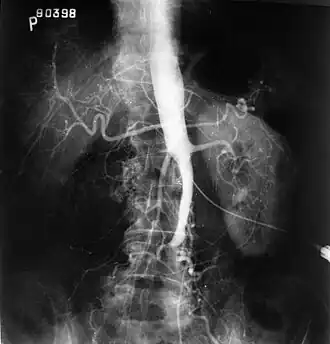

O exame físico geralmente mostra pulsos femorais enfraquecidos e um índice tornozelo-braquial reduzido. O diagnóstico pode ser verificado pela digitalização em duplex em cores, que revela uma taxa de velocidade sistólica de pico ≥2,5 no local da estenose e/ou uma forma de onda monofásica. A angiografia por ressonância magnética e a angiografia por tomografia computadorizada múltiplo detector são frequentemente usados para determinar a extensão e o tipo de obstrução. Outra técnica é a angiografia por subtração digital, que permite a verificação do diagnóstico e tratamento endovascular em uma única sessão.[1] A angiografia fornece informações importantes sobre a perfusão e perviedade das artérias distais (por exemplo, artéria femoral). A presença de artérias colaterais na região pélvica e na virilha é importante para manter o fluxo sanguíneo crucial e a viabilidade dos membros inferiores. No entanto, a angiografia deve ser usada apenas se os sintomas justificarem intervenção cirúrgica.